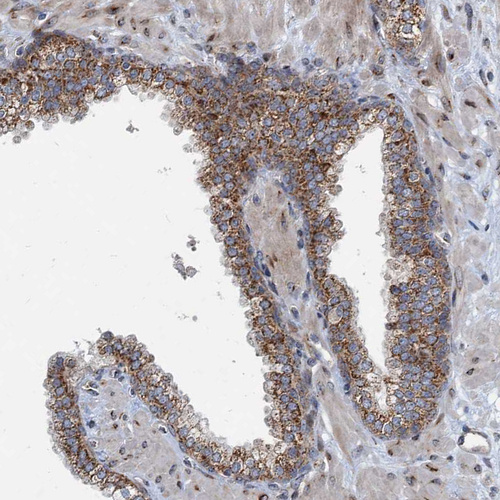

Immunohistochemical staining of human kidney, liver, placenta and prostate using Anti-CEP68 antibody HPA040620 (A) shows similar protein distribution across tissues to independent antibody HPA040493 (B).